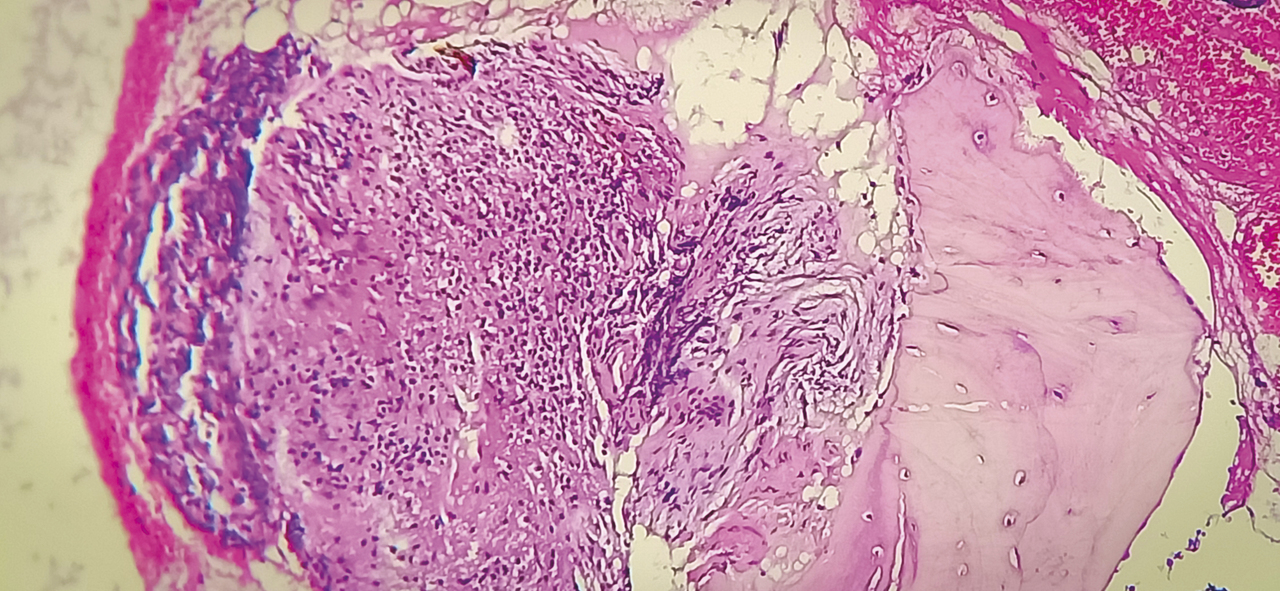

Cet homme de 53 ans consultait pour une douleur de la charnière dorsolombaire à irradiation antérieure, mal calmée par les antalgiques, avec un amaigrissement sans fièvre. L’examen clinique trouvait une raideur rachidienne et le bilan biologique montrait un syndrome inflammatoire. La tomodensitométrie (TDM) abdominale révélait une fibrose rétropéritonéale avec lyse de L1 (fig. 1 ). L’imagerie par résonance magnétique (IRM) montrait un aspect de fibrose rétropéritonéale secondaire, en hyposignal T1 et T2, se rehaussant après injection du gadolinium avec lyse de L1 (fig. 2 ). La tomographie par émission de positons au 18-fluorodésoxyglucose (TEP18-FDG) montrait un hypermétabolisme intense de L1 dont la biopsie scannoguidée révélait un granulome épithélio-giganto-cellulaire cadrant avec une tuberculose (fig. 3 ). Le patient était efficacement traité par les antibacillaires pendant 9 mois.

La fibrose rétropéritonéale est caractérisée par la présence d’un tissu fibro-inflammatoire aberrant engainant les gros vaisseaux et les uretères. À côté de la forme idiopathique, il existe des formes secondaires à des médicaments, à un anévrisme de l’aorte, à un cancer et aux infections.1 La biopsie est indiquée devant l’existence d’un tissu anormal entre l’aorte et les vertèbres avec déplacement antérieur des gros vaisseaux ou d’un en- vahissement des structures adjacentes.1 La TEP18-FDG per-met de déceler la présence d’un processus cancéreux ou infectieux accessible à la biopsie.1 La fibrose rétropéritonéale secondaire à la tuberculose est rare, les sites rapportés de tuberculose sont : le rachis, le rein et les ganglions.2 Les mécanismes de genèse de la fibrose pourraient être en rapport avec l’auto-immunité provoquée par la tuberculose.2